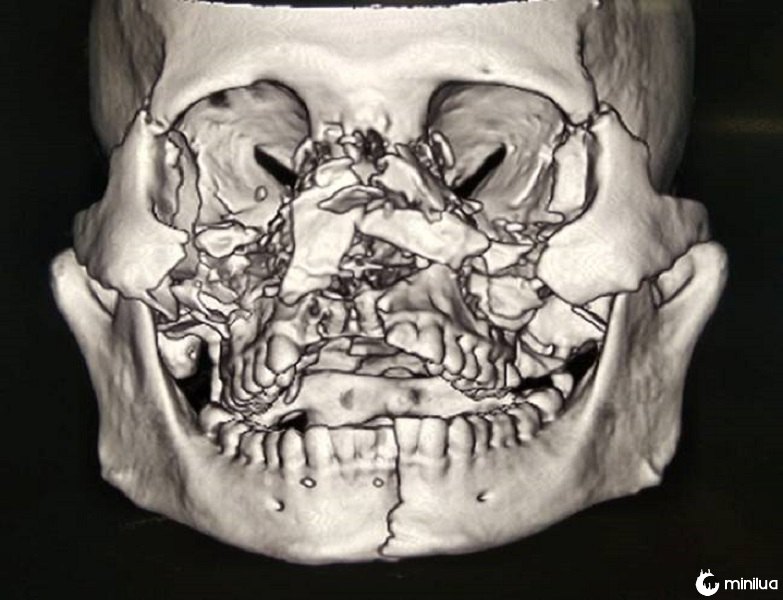

O Dr. Ghosh explicou: "Toda a sua estrutura facial estava distorcida e os ossos da face estavam em pedaços.

"O que tornou mais difícil foi que todos os ossos do meio do rosto foram esmagados e em pedaços pequenos."

"Não houve apoio no rosto.

"Ambas as órbitas sofreram fraturas com hérnia de gordura no seio.

"O nariz estava completamente aberto e aberto ao seio.

"O palato também estava dividido em duas partes. Até a mandíbula estava fraturada".

Ele continuou: "Então a ruptura orbital foi reparada e revestida. Finalmente, os tecidos moles dos lábios e nariz foram reconstruídos."